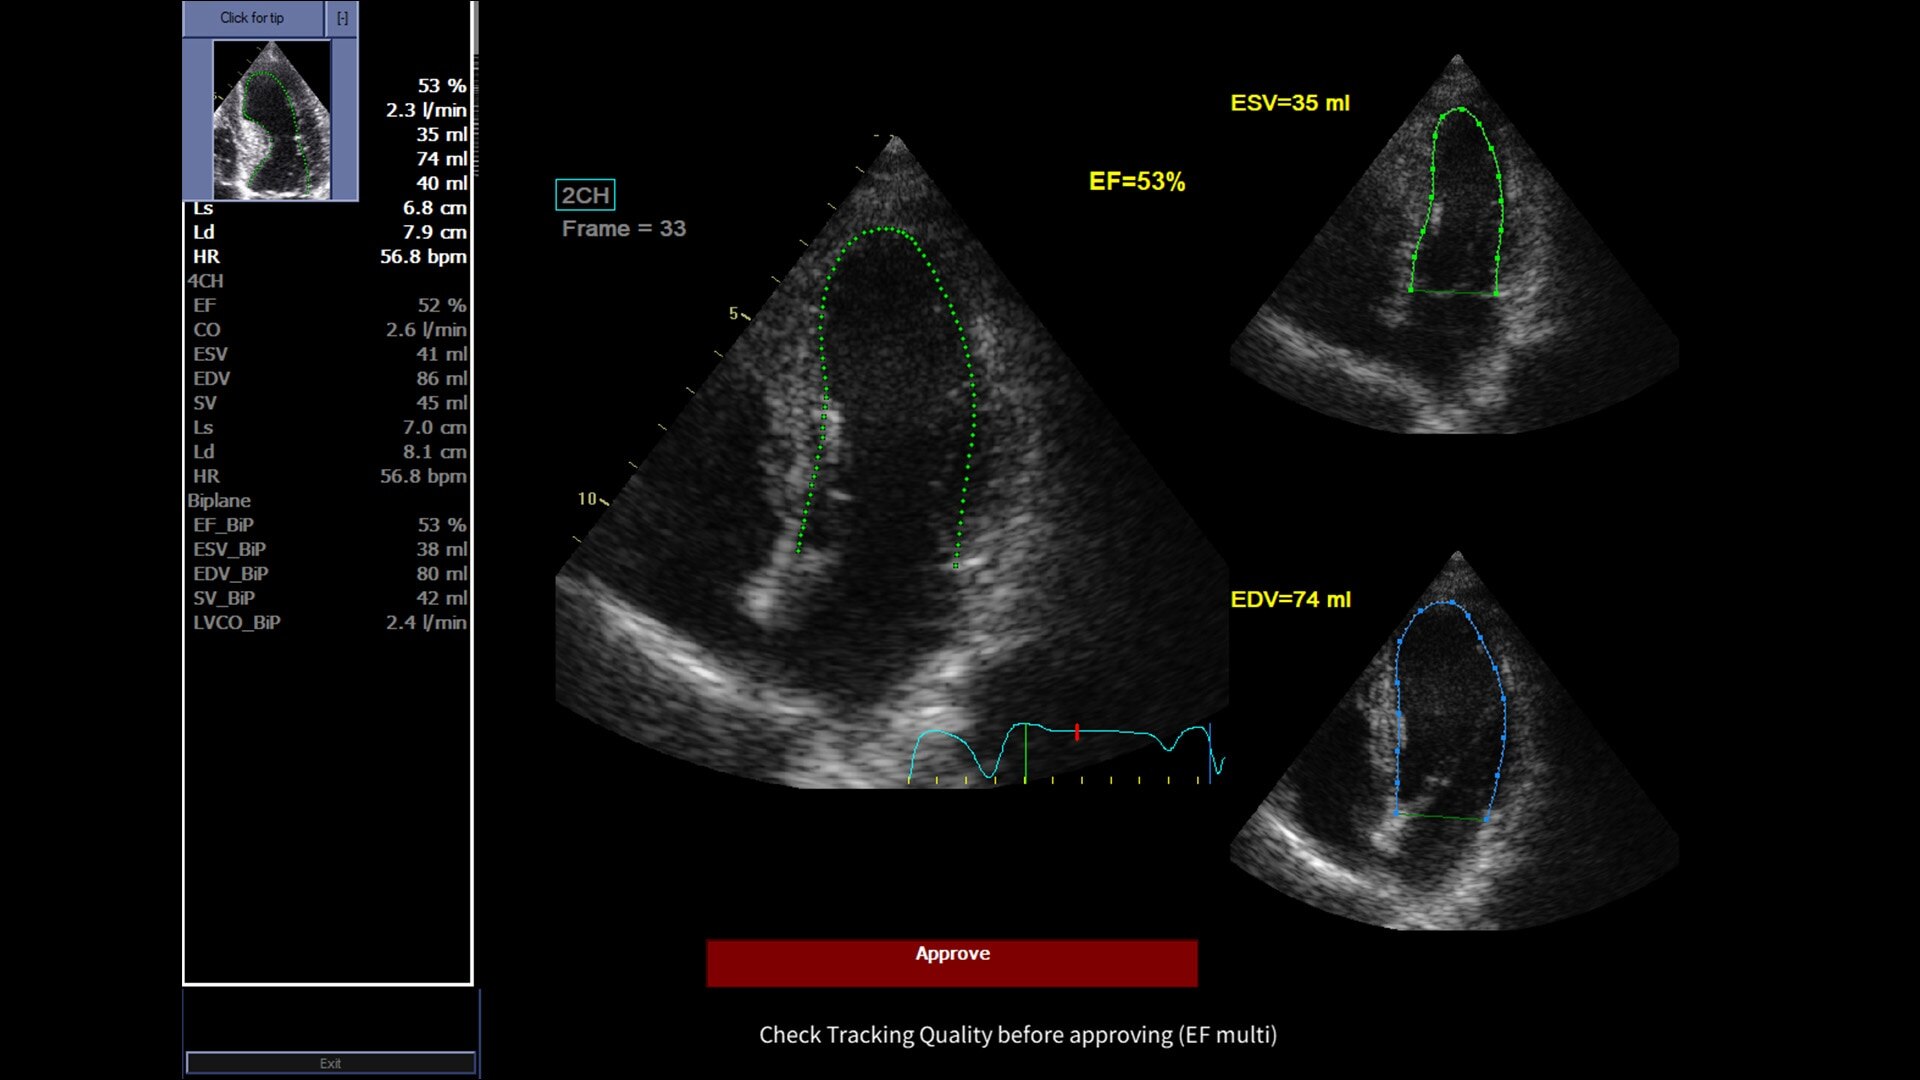

Powered by VisionBoost Architecture, Versana Premier provides optimal image quality so users can easily reach a diagnosis. Advanced clinical features help address challenging cases while automated tools help reduce scan time:

• Optimize images while scanning with Whizz clinical features, easily improve Color Doppler with Whizz Color Flow, and view scans in the image style that suits your preference with Whizz Easy Style

• Use automated labeling in the RUQ with Whizz Label

• Make automated 2D Measurements and Volume Calculations with Auto Contour, Auto Bladder, Whizz Follicle and Auto-IMT

• Assess liver, thyroid and breast nodules with Productivity Packages leveraging LI-RADS,® TI-RADS® and BI-RADS® criteria*